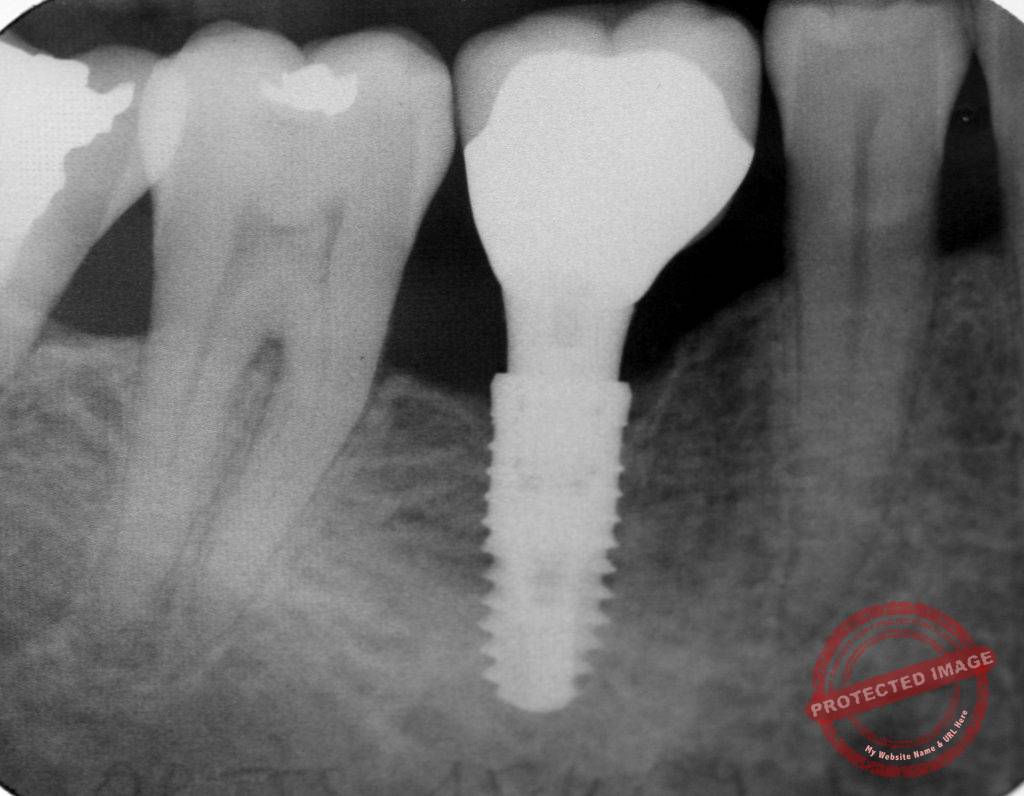

나이가 들면서 치아를 상실하는 사람들도 늘어나고, 자연 치아를 대체하기 위한 의료 기술도 발전하고 있습니다. 그중 가장 대표적인 것이 바로 치아 임플란트입니다. 우리나라도 이러한 흐름에 맞춰 임플란트에 대한 건강보험 급여화가 확대되고 있습니다.

임플란트는 뼈에 나사를 심어서 치아를 회복하는 것이기에 뼈에 대해 살펴보겠습니다. 사람의 골격은 30세까지 뼈가 단단해지다가 그 이후엔 뼈가 점점 약해져서 50대가 넘어가면 여성의 경우엔 10%, 남성의 경우엔 2% 정도 뼈의 강도가 감소합니다.

2018년 이만 등이 보철학회 저널에 게재한 연구결과를 보겠습니다. 1071명의 환자에서 뼈의 강도에 따라 5년간 임플란트 생존율을 비교하였습니다. 그 결과 강도가 낮은 뼈나, 일반적인 뼈나 둘 다 임플란트 생존율에는 차이가 없었습니다. 하지만 임플란트 식립 시에 더 주의를 요한다고 하였습니다.

즉, 나이가 들어 뼈의 강도가 감소하여도, 수술 시 주의를 좀 더 하면 임플란트 성공에는 영향이 없다는 것입니다.